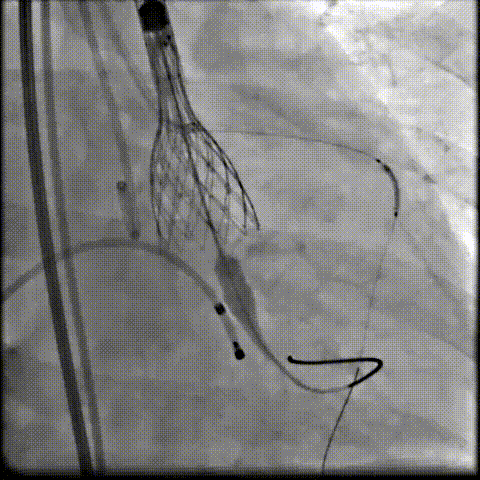

术中影像

根部造影可见返流,23mm球囊预扩张

无窦侧严重钙化及融合影响,

瓣膜(AV29)释放不稳出现反复上跳,2次回收尝试

重新定位释放,

钙化及融合挤压导致瓣膜(AV29)下滑位置偏深

第三次回收重新定位

工作位造影位置良好,完全脱钩释放瓣膜(AV29)

考虑支架腰部挤压,23mm球囊充分后扩后形态良好,

极微量瓣周漏